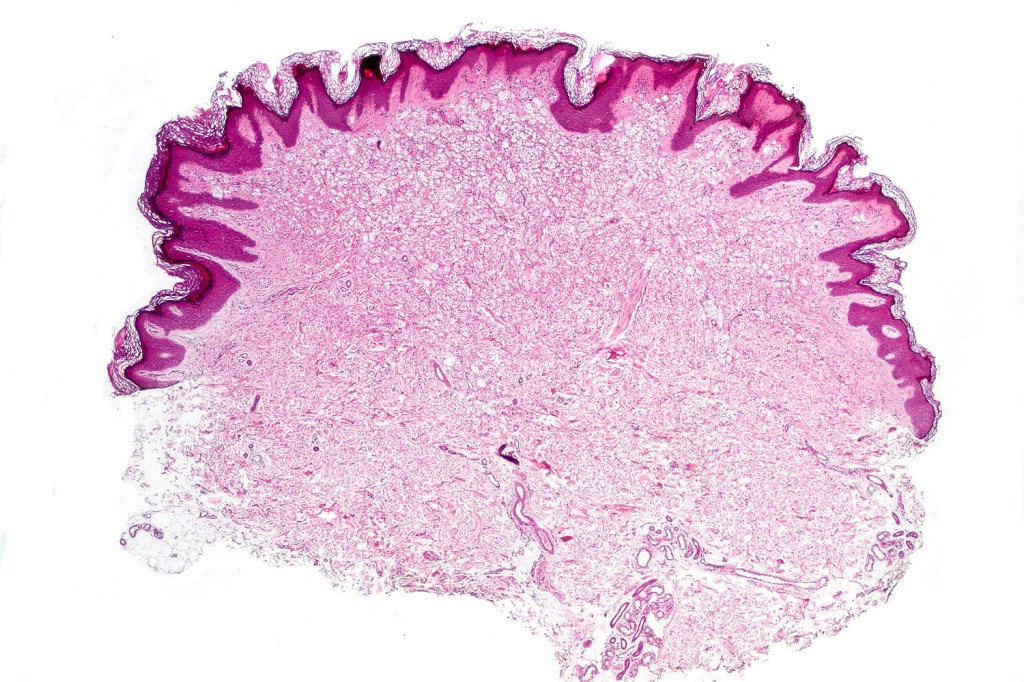

Balloon cell nevus represents the benign counterpart of balloon cell melanoma.

Histological features

.Balloon cell change is most often seen in banal melanocytic nevi but it has also rarely been described in cellular blue nevus, dysplastic nevus, combined nevus, halo nevus & Spitz nevus. Lesions with <50% of balloon cells are sometimes described as nevi with balloon cells. Nevi with >50% balloon cells are described as balloon cell nevus.